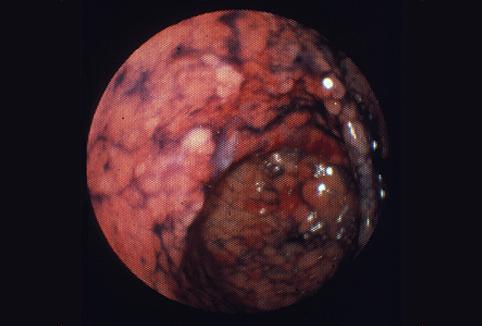

clasificación del pacienteTumor Epitelial Maligno/Adenocarcinoma

parte(separada por órganos)estómago(región)/antro

método de exámenEndoscopia

clasificación ectoscópica de tumoresTipo 0(tipo superficial)/Tipo IIa(IIa+IIc)

diámetro mayor del tumor25 - 29

grado de penetraciónm